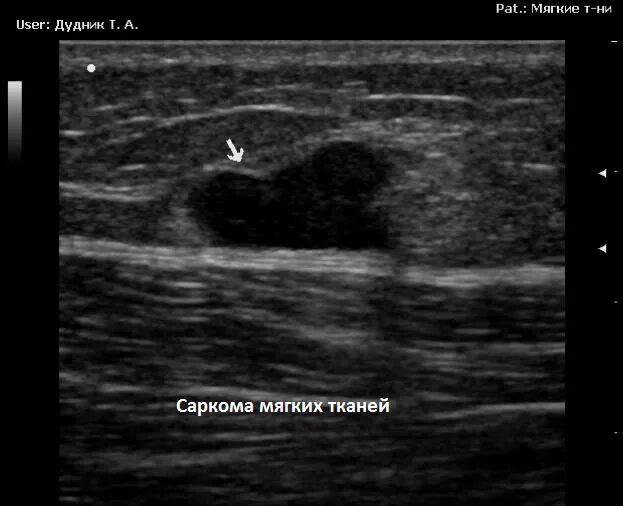

Филлеры на узи